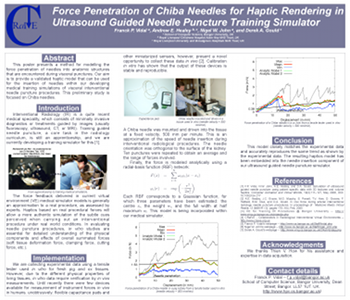

F. P. Vidal, A. E. Healey, N. W. John, and D. A. Gould.

Force penetration of chiba needles for haptic rendering in ultrasound

guided needle puncture training simulator.

In MICCAI 2008 - Workshop on Needle Steering: Recent Results

and Future Opportunities, New York, September 2008.

Available at http://lcsr.jhu.edu/NeedleSteering/Workshop/Vidal.html.

F. P. Vidal, A. E. Healey, N. W. John, and D. A. Gould.

Force penetration of chiba needles for haptic rendering in ultrasound

guided needle puncture training simulator.

In MICCAI 2008 - Workshop on Needle Steering: Recent Results

and Future Opportunities, New York, September 2008.

Available at http://lcsr.jhu.edu/NeedleSteering/Workshop/Vidal.html.